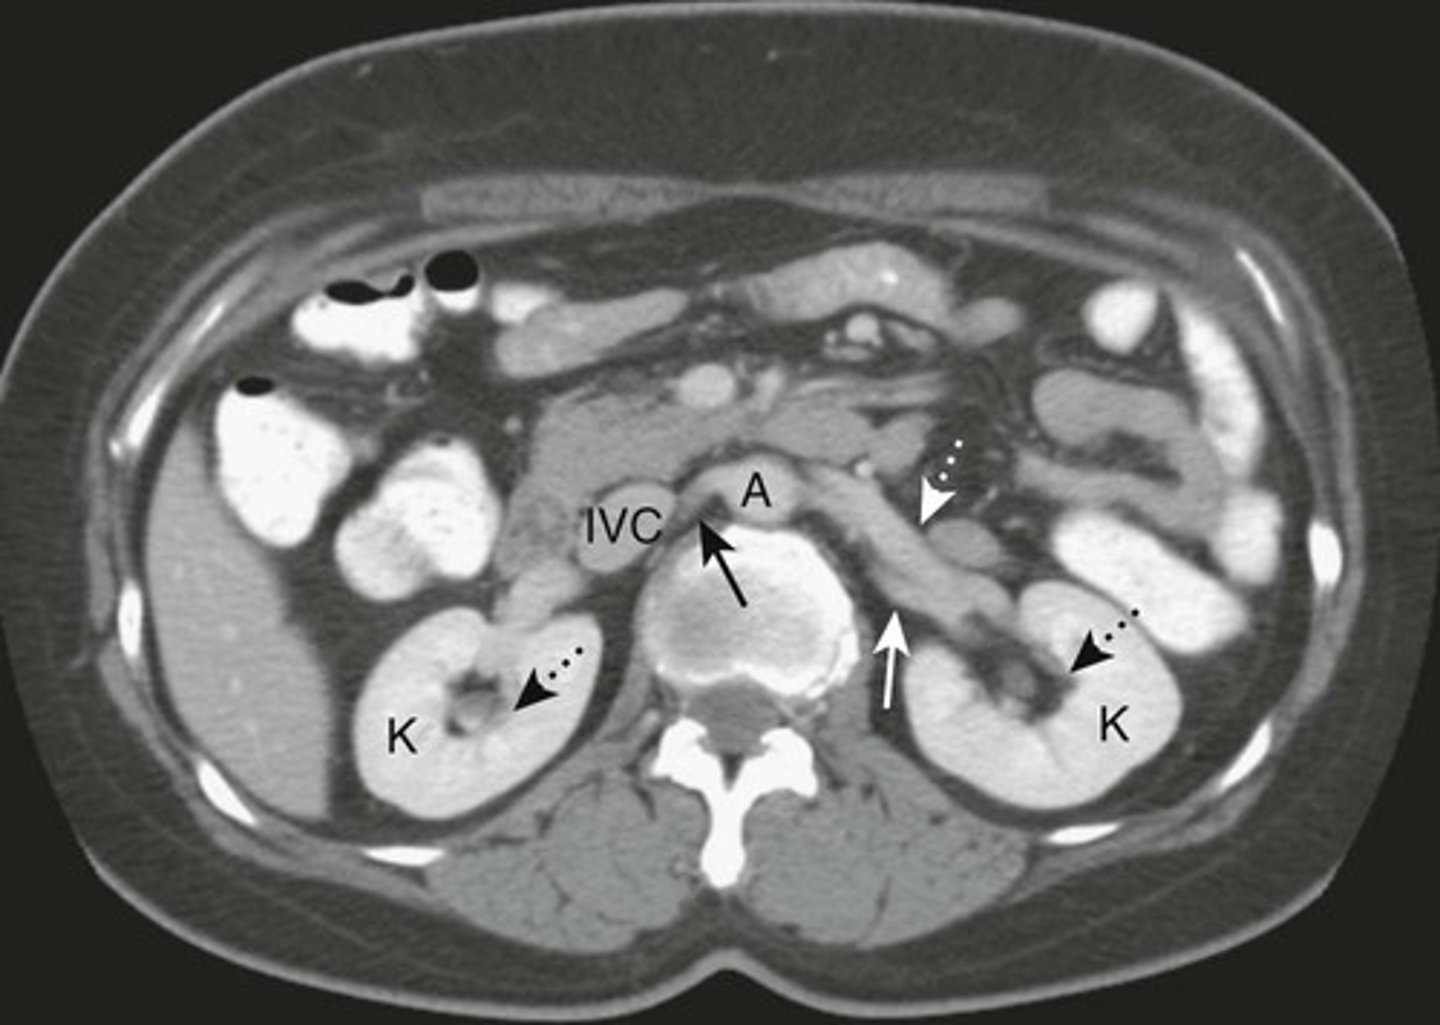

Normal Kidneys

K: Kidneys, lie in the renal fossae

DOTTED BLACK ARROWS: Central portion of the kidneys, should contain fat in a normal renal pelviz.

SOLID BLACK ARROW: Right renal artery, running posterior to the IVC

DOTTED WHITE ARROW: Left renal vein, lies anterior to the left renal artery.

SOLID WHITE ARROW: left renal artery.

A: Abdominal Aorta

IVC: inferior vena cava